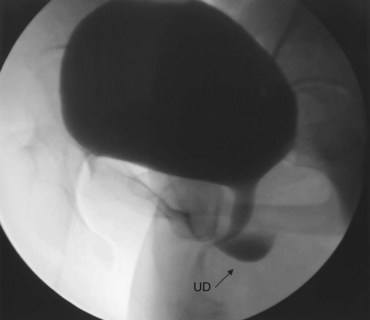

As an alternative to PPU, VCUG may provide excellent imaging of UD (Fig. 78–20). It is widely available and is a familiar diagnostic technique to most radiologists. Sensitivity for UD with this technique varies from 44% to 95% (Ganabathi et al, 1994; Jacoby and Rowbotham, 1999). Patients often will have difficulty in initiating micturition in the radiology suite due to the pain associated with urethral catheterization, psychogenic inhibition due to voiding in the presence of others, or other factors. In the absence of voiding, the urethral diverticulum will not be seen. Therefore a VCUG which does not demonstrate a urethral diverticulum but did not contain voiding images or postvoid images is nondiagnostic. If the patient is unable to void under fluoroscopy during the VCUG, an attempt should be made to void in the privacy of an adjacent bathroom. If voiding in private was successful, a postvoid film taken under these circumstances will likely show a collection of contrast inferior to the bladder demonstrating the urethral diverticulum. Unfortunately, an inability to generate an adequate flow rate during the VCUG will result in suboptimal filling of the UD and an underestimation of its size and complexity (Fig. 78–21). Three-dimensional CT VCUG with reconstructions is being investigated as a novel imaging technique for UD but is not yet widely available clinically (Kim et al, 2005).

Figure 78–20 Voiding image from a voiding cystourethrogram demonstrating a urethral diverticulum (UD).

Figure 78–21 Voiding cystourethrogram (VCUG) and MRI from a patient with a large circumferential urethral diverticulum (UD). The voiding image from the VCUG (A) shows poor opacification of the proximal urethra with suboptimal distention of the UD due to a poor voiding effort. The endoluminal MRI demonstrates the full extent and complexity of the lesion on the T2 axial (B), midline sagittal (C), and parasagittal (D) images.